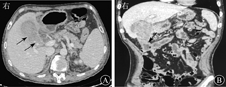

入院后体格检查:血压122/73 mmHg(1 mmHg=0.133 kPa),体温为36.8 ℃,心率为83次/min,呼吸频率为21次/min,皮肤和巩膜轻度黄染,心肺未见异常,右上腹压痛,无肌紧张,无反跳痛,墨菲征阴性。血常规示血白细胞计数为10.9×109/L,血红蛋白为120 g/L。肝功能检查示ALT为57 U/L,AST为28 U/L,GGT为214 U/L,TBil为23.90 μmol/L,DBil为19.1 μmol/L,凝血功能、肾功能、血电解质、粪便常规和尿常规等均正常,胸部X线片和心电图均正常。考虑患者为胆囊结石、胆囊炎可能性大,但需排除胆总管结石,遂行腹部超声、CT和磁共振胰胆管造影(magnetic resonance cholangiopancreatography, MRCP)检查。腹部超声检查提示为胆囊结石(填满型);CT检查提示胆囊异常强化灶,考虑肿瘤性病变、胆囊结石,胆囊与结肠密切相连,见图1;MRCP检查提示胆囊多发结石并发胆囊炎,胆囊壁增厚,胆囊与结肠紧密相连,见图2;故诊断为胆囊结石伴急性胆囊炎或胆囊肿瘤,遂拟行腹腔镜胆囊切除术。